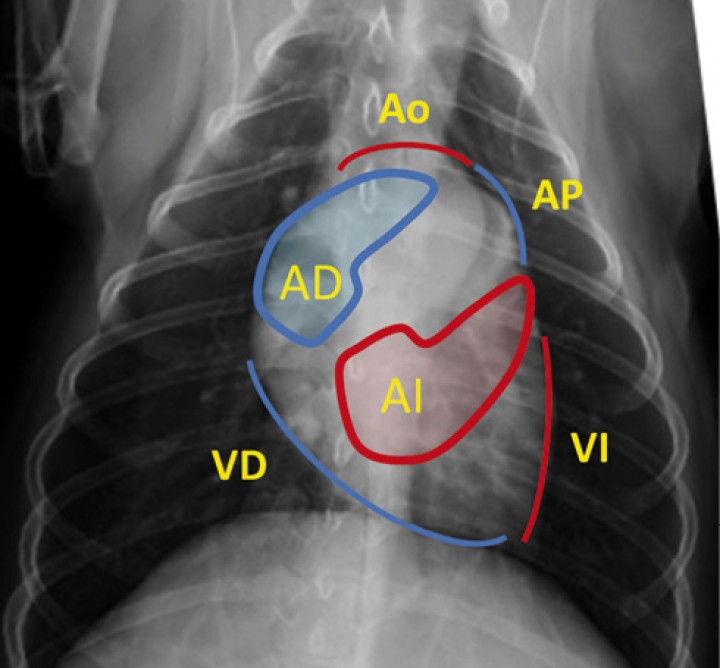

<p>Proyección dorsoventral con diagrama de la localización anatómica de las distintas cámaras y grandes vasos. En color azul se representa corazón derecho y en color rojo corazón izquierdo. Ao: aorta. AP: arteria pulmonar. AD: atrio derecho. AI: atrio izquierdo. VD: ventrículo derecho. VI: ventrículo izquierdo.</p>

Proyección dorsoventral con diagrama de la localización anatómica de las distintas cámaras y grandes vasos. En color azul se representa corazón derecho y en color rojo corazón izquierdo. Ao: aorta. AP: arteria pulmonar. AD: atrio derecho. AI: atrio izquierdo. VD: ventrículo derecho. VI: ventrículo izquierdo.